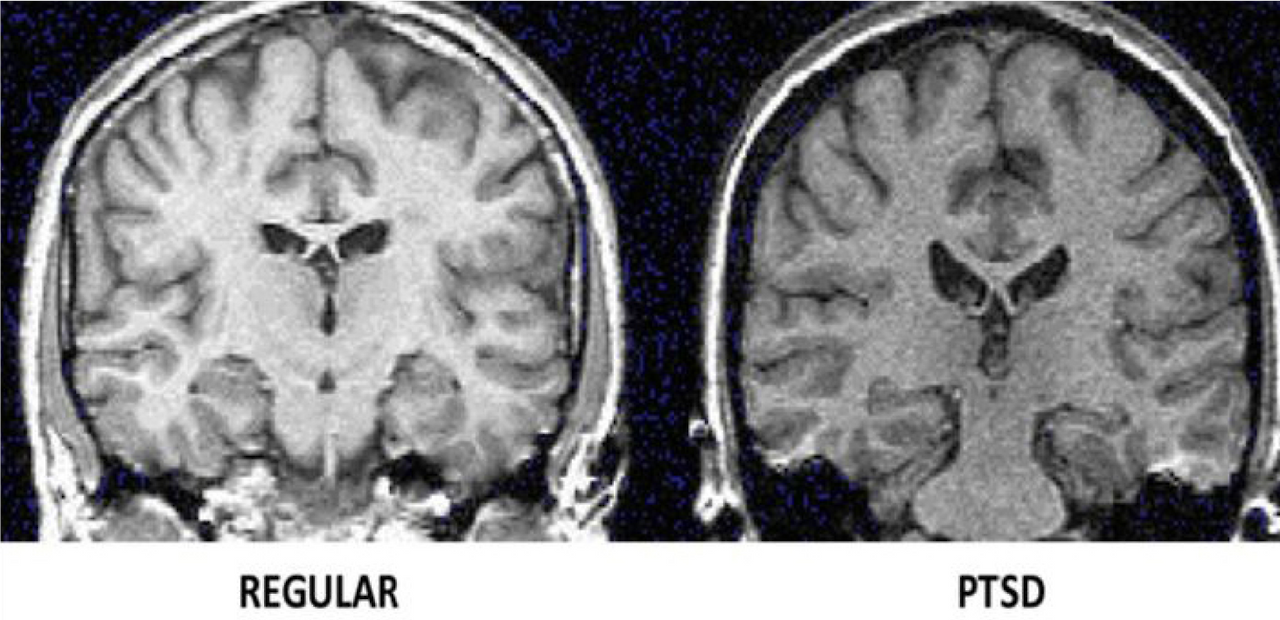

'외상 후 스트레스 장애(PTSD)'는 트라우마로 쉽게 이해되는데 이러한 트라우마는 보이지 않는 심리적인 요인만 영향을 미치는 것이 아니라 물리적인 형태에도 영향을 미친다. 데이비스 에머슨의 저서 트라우라 치유 요가에서 이러한 근거를 설명하고 있다. 웨스턴 온타리오 대학교 정신과 교수 루스 래니우스와 그의 동료들의 연구에서 외상 후 스트레스를 가진 사람들이 비교집단에 비해 뇌 활동 수준이 낮았으며 외상 스트레스가 있는 참전군인이 포함된 다른 연구에서는 비교집단에 비해 섬엽과 대상피질의 회백질 크기가 더 적은 것으로 발견되었다.

트라우마 영향으로 물리적 문제가 발생한 뇌 부위는 많은 감각정보가 입력될 수 있도록 다양한 인지 운동이 필요하다. 2011년 트라우마를 가진 성인 8명을 대상으로 한 연구에서 6명은 20주간 TSY(트라우마 치유요가)를 참여하고 하였고 나머지 2명은 참여하지 않았는데 fMRI(기능적 자기공명영상) 사전, 사후 검사에서 요가를 한 6명이 그렇지 않은 2명에 비해 내부수용감각 활동 증가를 검증할 수 있었다.